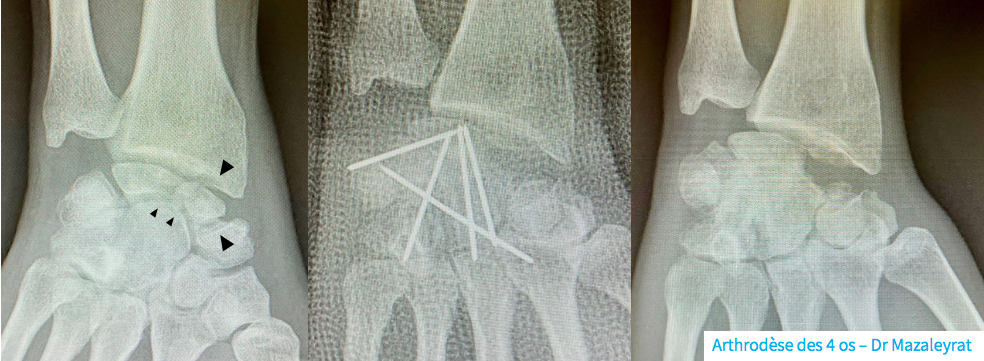

- L’arthrodèse partielle limitée à seulement certains os du carpe (2, 3, 4 os du carpe avec scaphoïdectomie) ou parfois radiocarpienne. Les interlignes pathologiques sont fusionnées et fixées par des broches, une plaque, des vis ou des agrafes.

La cicatrisation demande environ 2 semaines. La mobilisation des doigts est immédiate. Le poignet peut être immobilisé pendant une durée de 8 semaines en cas d’arthrodèse. Une rééducation par un kinésithérapeute peut être prescrite selon l’avis du Dr Laporte ou du Dr Mazaleyrat. La surveillance ultérieure des pansements, la couverture anti-douleurs ainsi que les rendez-vous de contrôle avec radiographie vous seront donnés par le secrétariat du Dr Laporte ou du Dr Mazaleyrat.